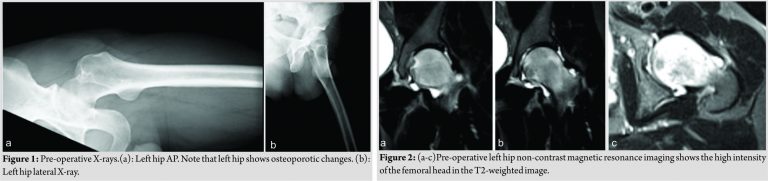

A 33-year-old male patient presented to orthopedics and traumatology outpatient clinic with left hip pain. The pain started suddenly 3 months ago while walking and the patient were conservatively treated. Due to pain did not subside despite conservative therapy, magnetic resonance imaging (MRI) scan was performed. It showed bone marrow edema of the left femoral head, and consequently, the patient was referred to our tertiary clinic to have surgery. Patient’s history was significant for palpitations, itching after the bath and episodic chest pain starting approximately 3 months ago. The patient also complained of paresthesias at the hands, feet, and back of the neck 6–7 months ago and his medical history was unremarkable including steroids, and he did not have any concomitant diseases. Patients medical and surgical history were unremarkable; however, family history was positive for a hematological malignancy in his sibling. The patient was using crutches. Inspection of the hips and lower extremities was normal. Passive flexion and extension of the left hip elicited pain with normal range of motion. Internal rotation of the left hip was painful and restricted, while external rotation was normal with the full range of motion. The neurovascular examination was unremarkable. The anterior-posterior and lateral X-ray of the hips were taken (Fig. 1).

MRI shows increased intensity on T2-weighted images (Fig. 2). Patient’s complete blood count (CBC) done at another hospital showed thrombocyte count of 609 103/µL whereas other parameters were in normal range. At the time of presentation, CBC was normal except the thrombocyte level (644 103/µL). Considering the presenting symptoms and diagnostic tests of the patient, the initial diagnosis was established as ET, hematology opinion obtained. A genetic analysis was positive for JAK2 V617F. Repeated hemograms during the follow-up showed increasing thrombocyte counts (665 103/µL and 769 103/µL, respectively) which support the diagnosis. To prevent possible thrombotic complications, the patient was started on acetylsalicylic acid and hydroxyurea and the patient has scheduled a bone marrow biopsy. While protein electrophoresis was normal, bone scintigraphy showed significantly increased activity in the left femoral head and acetabular region. The patient was diagnosed with TO of the hip and core decompression was planned to eliminate compressive symptoms of the hip.